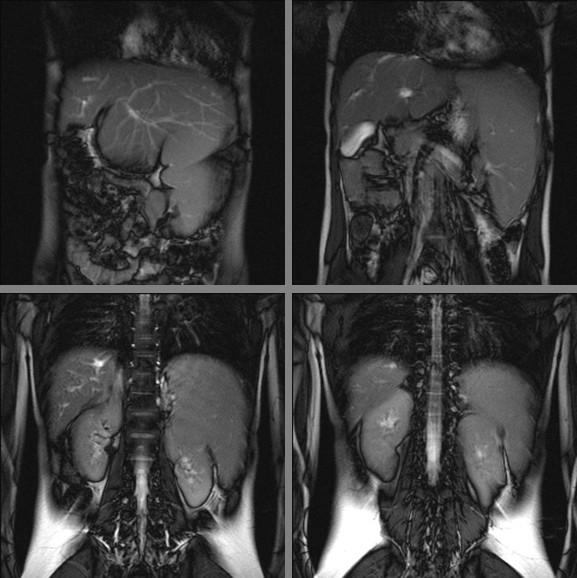

Congenital hepatic fibrosis (CHF) is a rare autosomal recessive disease that primarily affects the hepatobiliary and renal systems. It is characterized by hepatic fibrosis, portal hypertension, and renal cystic disease. Firm or hard hepatomegaly is present nearly in all patients, often with a prominent left lobe, and this is usually one of the presenting signs. The haematological manifestations due to hypersplenism generally arise when the other gastrointestinal manifestations are clearly developed. We describe the first case of CHF presenting in an otherwise healthy child, with thrombocytopenia and splenomegaly as the only manifestations of the disease.

先天性肝纤维化(CHF)是一种罕见的常染色体隐性遗传病,主要影响肝胆和肾脏系统。其特征是肝纤维化、门静脉高压和肾脏囊性疾病。几乎所有患者都存在肝脏肿大、质地坚硬,通常左叶更为显著,这通常是其主要表现之一。由于脾功能亢进引起的血液学表现通常在其他胃肠道表现明显出现时才会发生。我们描述了首例表现为健康儿童的 CHF 病例,其仅表现为血小板减少和脾肿大。